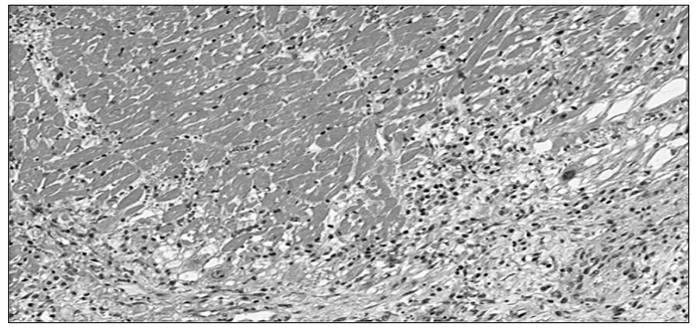

A imagem microscópica abaixo representa o corte histológico de uma lesão localizada na parede anterior do ventrículo esquerdo, encontrada

no exame de necrópsia de um paciente de 48 anos de idade, sexo masculino, encontrado em óbito no seu domicílio:

Mediante as informações e a análise microscópica acima, assinale a alternativa correta.